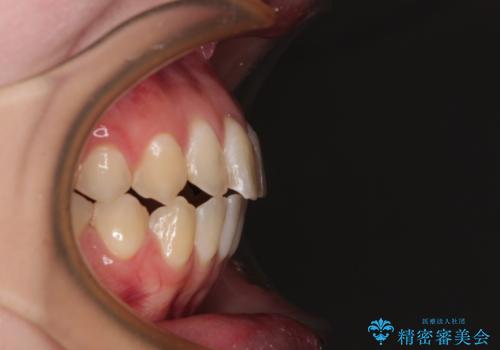

開咬を治す インビザラインによる矯正治療

- 上下前歯の開咬を気にして来院された患者様です。

開咬はインビザラインを用いると有意に改善ができるため、インビザラインによる矯正治療を行うこととしました。